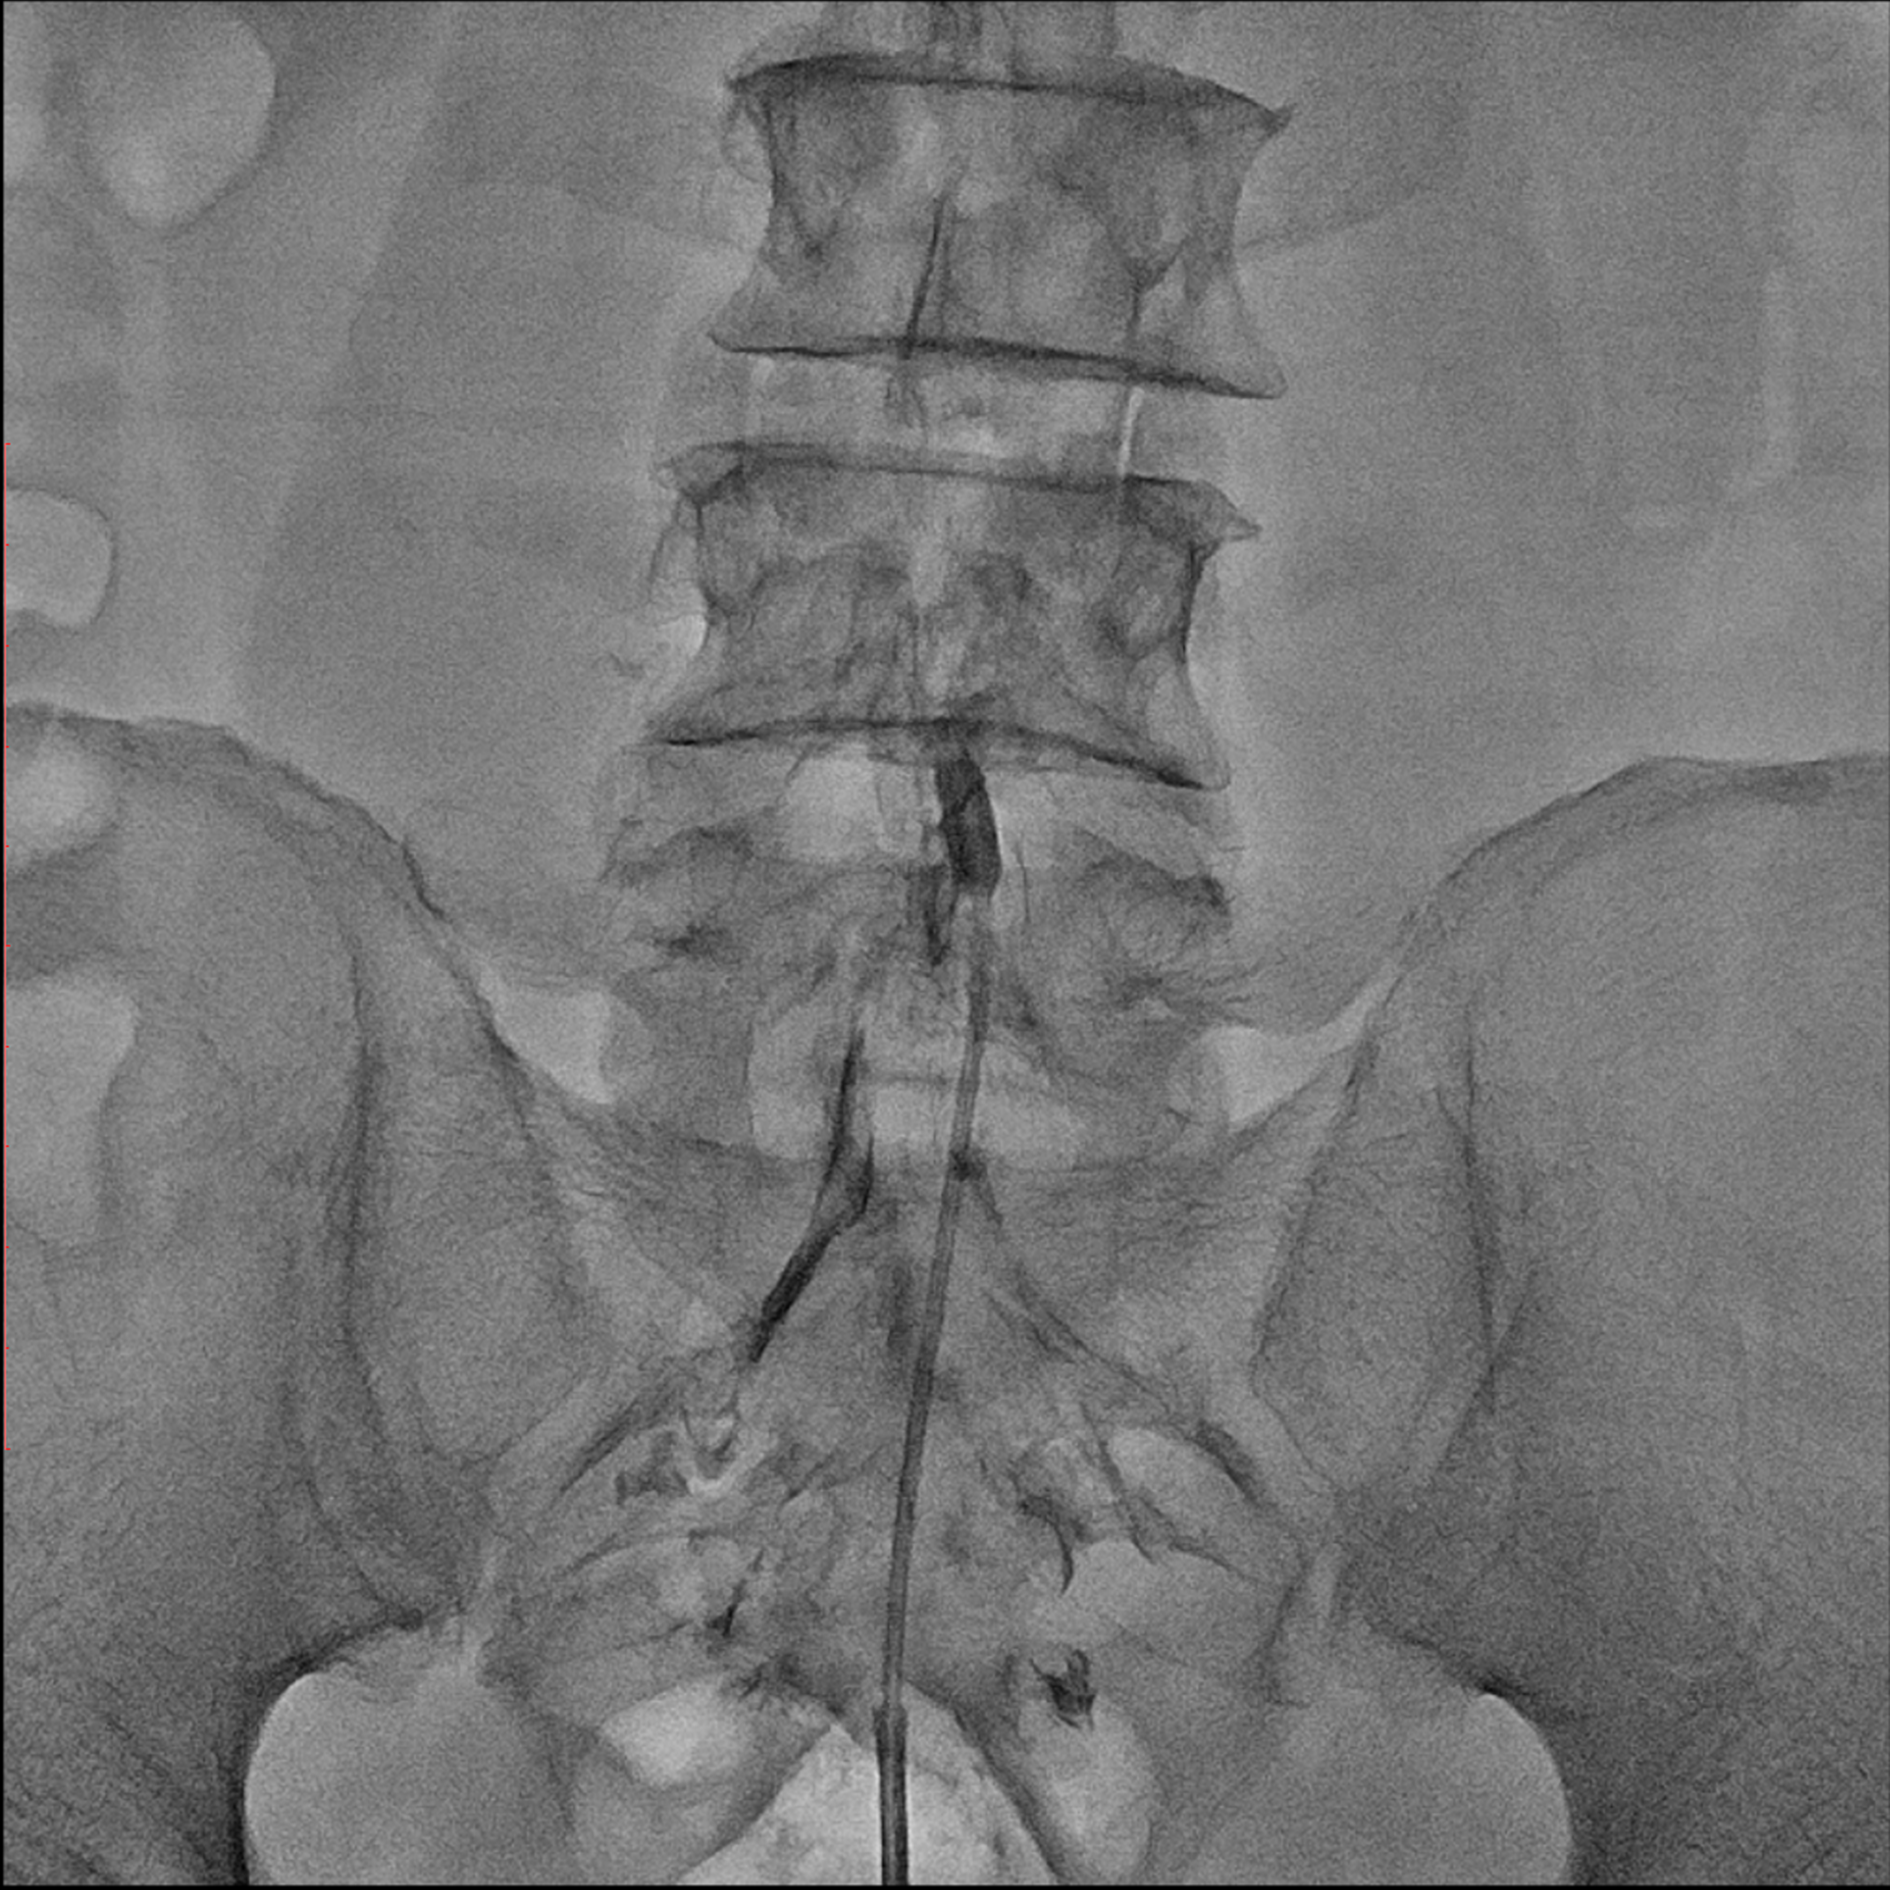

Editorial/Editor's Pick 경막외 유착박리술, Epidural Neuroplasty by Pharmacopuncture Research Lab 2026. 1. 3. 공유하기 게시글 관리 Acupuncture Radiology 관련글 MRI 요양급여의 적용기준 및 방법에 관한 세부사항 MRI 요양급여의 적용기준 및 방법에 관한 세부사항 [신구대조표] Association of AI‑determinedKellgren–Lawrence grade Portable X-ray